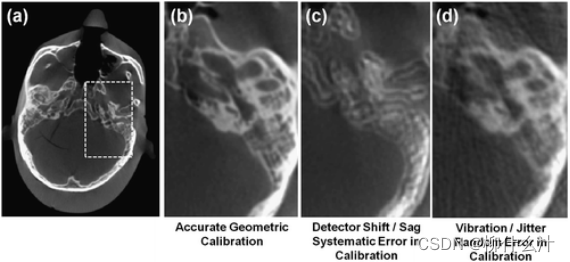

准确的图像重建需要对成像系统的几何形状进行校准。几何校准的错误可能表现为图像重建中的条纹和/或失真。FPDs基本上没有失真,而X射线图像增强器通常需要额外的失真校正,以考虑到枕状效应,如下图1所示。对于扫描轨道中的每个投影,几何校准表征了X射线源和探测器的姿态,这对于重建过程中的精确背投至关重要。X射线源和探测器在扫描中遵循一个完美的圆形轨道并不重要,但轨道必须是可重复的,并由校准准确描述以避免伪影。下图2显示了与几何校准误差相关的伪影实例,该图显示了颞骨区域的头部模型的CBCT图像,有各种形式的可能的几何校准误差。这些图像是通过360°旋转获得的,如图2a,b所示,显示了骨质细节的良好可视化。图2c显示了与旋转中心位置或穿刺射线位置的系统性偏移有关的几何校准伪影,为360°采集创造了双重图像(为较短的扫描轨道创造了新月形伪影)。几何校准中的随机误差的结果,例如,对系统几何中的高频振动/抖动估计不足,如图2d所示,产生的条纹可能难以与其他来源的噪声和条纹伪影相区分。

几何校准误差引起的伪影的说明。(a, b) 具有精确几何校准的头部幻影图像。(c)与(b)相同的图像,用校准中的系统误差(即x射线位置的5个像素的移动)重建。(d)与(b)相同的图像,用校准中的随机误差(即关于x射线的真实位置的四个像素的标准偏差)重建。